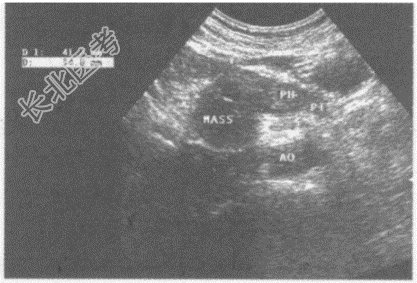

超声综合描述: 腹主动脉下腔静脉前方,胰头右侧可见3.6cm×3.4cm圆形低回声区, 边界清晰,包膜完整, 内回声尚均匀,CDFI: 内未明显血流信号,周边可见血管绕行。见下图及彩图。